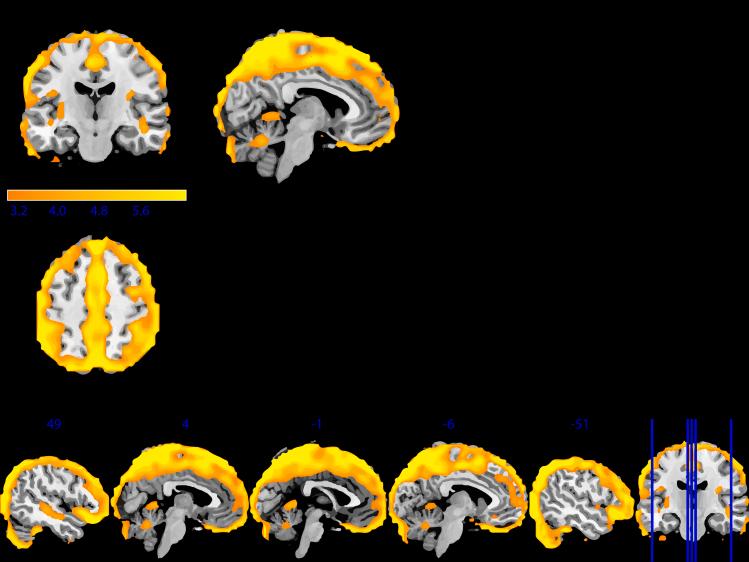

Structural neuroimaging studies have identified a combination of shared and disorder-specific patterns of gray matter (GM) deficits across psychiatric disorders. Pooling large data allows for examination of a possible common neuroanatomical basis that may identify a certain vulnerability for mental illness. Large-scale collaborative research is already facilitated by data repositories, institutionally supported databases, and data archives. However, these data-sharing methodologies can suffer from significant barriers. Federated approaches augment these approaches by enabling access or more sophisticated, shareable and scaled-up analyses of large-scale data. We examined GM alterations using Collaborative Informatics and Neuroimaging Suite Toolkit for Anonymous Computation, an open-source, decentralized analysis application. Through federated analysis of eight sites, we identified significant overlap in the GM patterns ( = 4,102) of individuals with schizophrenia, major depressive disorder, and autism spectrum disorder. These results show cortical and subcortical regions that may indicate a shared vulnerability to psychiatric disorders.

结构神经影像学研究已经确定了跨精神疾病的灰质(GM)缺陷的共享模式和特定疾病模式的组合。汇总大数据有助于检查可能的共同神经解剖学基础,这可能识别出精神疾病的某种易感性。数据存储库、机构支持的数据库和数据档案已经促进了大规模的合作研究。然而,这些数据共享方法可能存在重大障碍。联邦方法通过实现对大规模数据的访问或更复杂、可共享和可扩展的分析来增强这些方法。我们使用用于匿名计算的协作信息学和神经影像学套件工具包(一种开源、去中心化的分析应用程序)检查了灰质改变。通过对八个站点的联邦分析,我们在精神分裂症、重度抑郁症和自闭症谱系障碍患者的灰质模式(n = 4102)中发现了显著重叠。这些结果显示了可能表明对精神疾病存在共同易感性的皮质和皮质下区域。